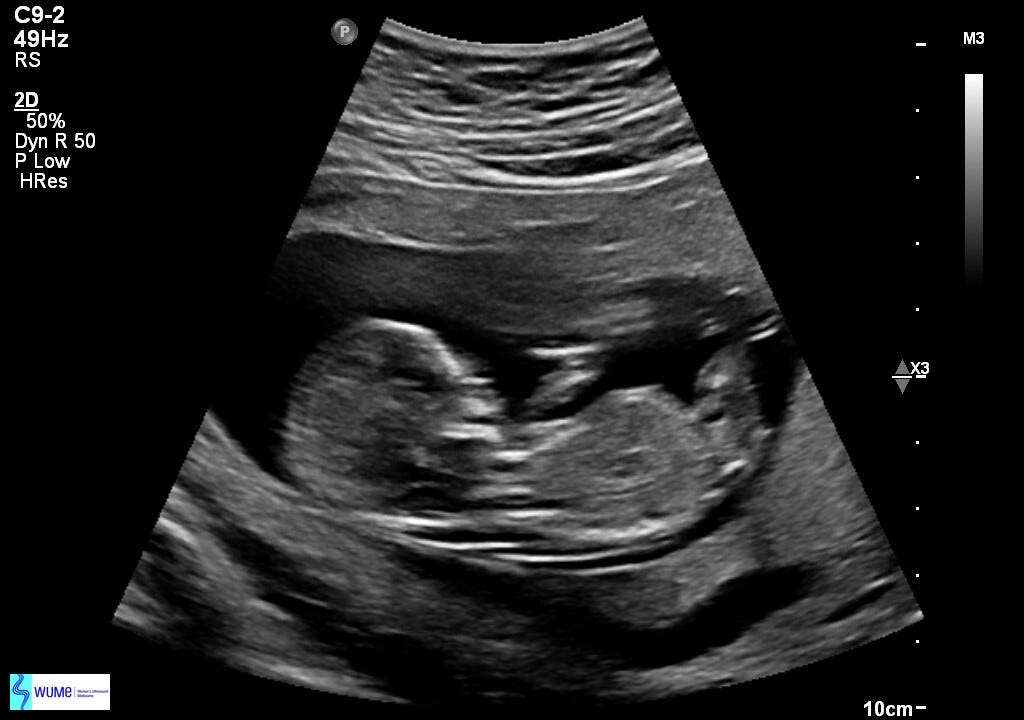

Dr Scott could not have been more amazing with this. Every scan (which was once a week) he would get Zo immediately on the bed and get our baby’s heart beat up on the monitor screen. You could physically feel the mood lighten each time and we would progress with the consultations. He and his team took the most care of Zoe (and I) during the first trimester and I could see why they are so highly recommended. We got well beyond the nine week mark and when the time was right, we could share the news with everyone.